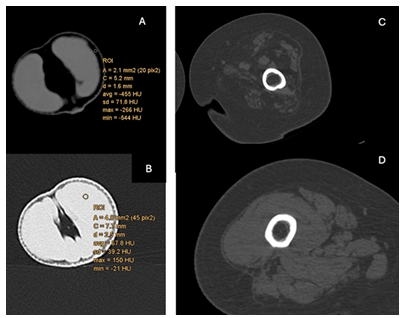

We evaluated density differences different models using Computed Tomography (CT) scanning. We compared a standard silicon suture pad (type and origin) against the tangerine / orange and the banana, our typically used home models, against structures like the aorta and skin. To ensure accuracy and comparability of our CT scan results, a calibration test of the CT scanner, using a standardized Hounsfield units (HU) phantom, was used. This step was crucial to account for potential variances between different CT scanners and to establish a baseline for HU measurements across all models.

The tangerine compares well with the structures of the femoral canal (Figure 2)

The suture pad’s density was recorded at approximately 265HU (Figure 3), the banana skin a was recorded at a maximum value of approximately 77HU, and the orange skin at a maximum value of approximately 304HU.

We mapped the standard deviation of HU values within each model to understand how uniformly density was distributed and to identify any areas of significant deviation from the reference tissue. This step was critical for evaluating the realism of each model in terms of tissue simulation (Figure 4)

The tangerine spills juice if the membranes are breached; the separation of the skin from the flesh, the segments from each other and then the skin from the segment, needs increasing skill and dexterity with the dissecting scissors. The appearance of juice, and maceration of the flesh offer immediate feedback.

Similarly, the tangerine model, with its unique structure, allows for the practice of dissection in subtle planes. These planes can be explored with dissecting scissors at various levels: removal of the skin, removal of a segment, and then removal of the segment skin to expose the flesh. The spilling of juice indicates transgression of tissue planes